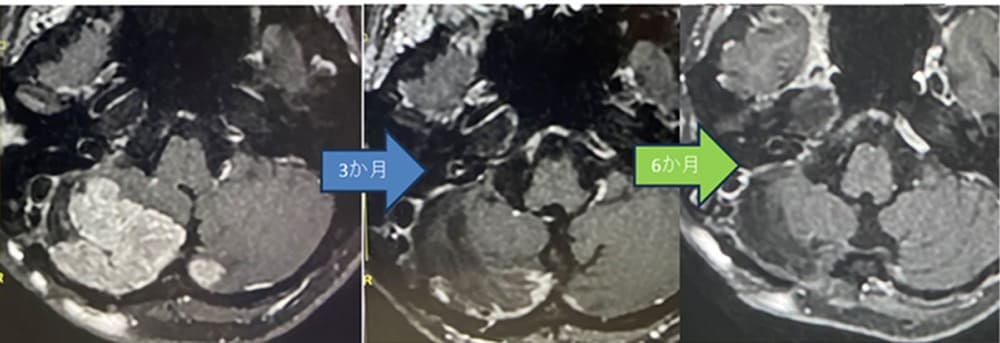

右小脳半球巨大転移性脳腫瘍(肺がん)症例の

ZAP-X治療後経過:3か月後(中)、6カ月後(右)